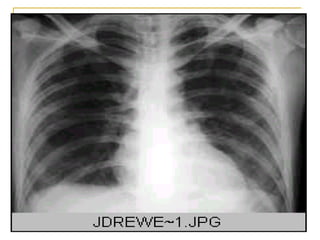

Infiltrado intersticial retículo nodular bilateral de predominio perihiliar y basal

Infiltrado intersticial retículonodular bilateral de predominio perihiliar y basal